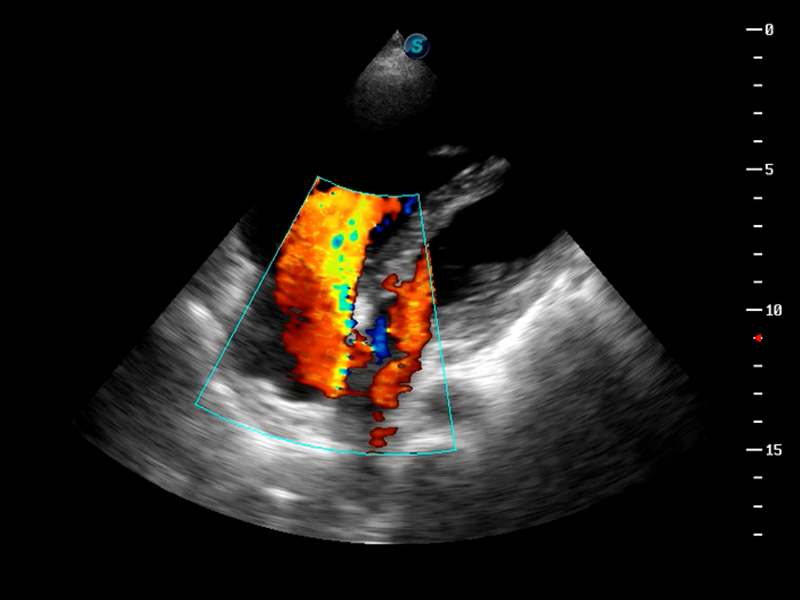

S9便携式彩色多普勒超声诊断仪是乐玩lewin国际研发的高端便携彩超设备,外观设计新颖、产品性能卓越。S9在便携超声领域采用了突破传统的触摸屏交互设计,并以先进的软件硬件技术和设计理念,为您带来清晰的图像质量、稳定的工作性能和便捷的操作体验。

TDI组织多普勒成像

造影成像